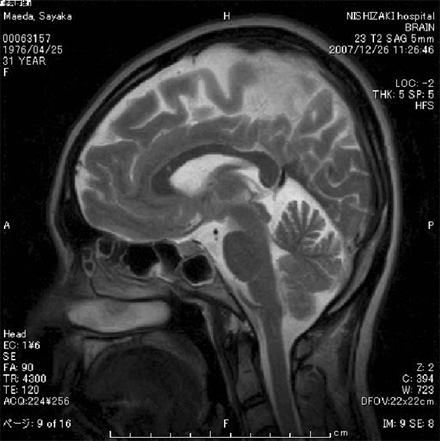

- 頭部MRI(磁気共鳴断層撮影)

- 脳出血・脳梗塞・脳腫瘍・慢性硬膜下血腫等の診断に有用です。

又、脳の萎縮等、認知症の診断にも役立ちます。 - 頭部MRA(MRIを用いた脳血管撮影)